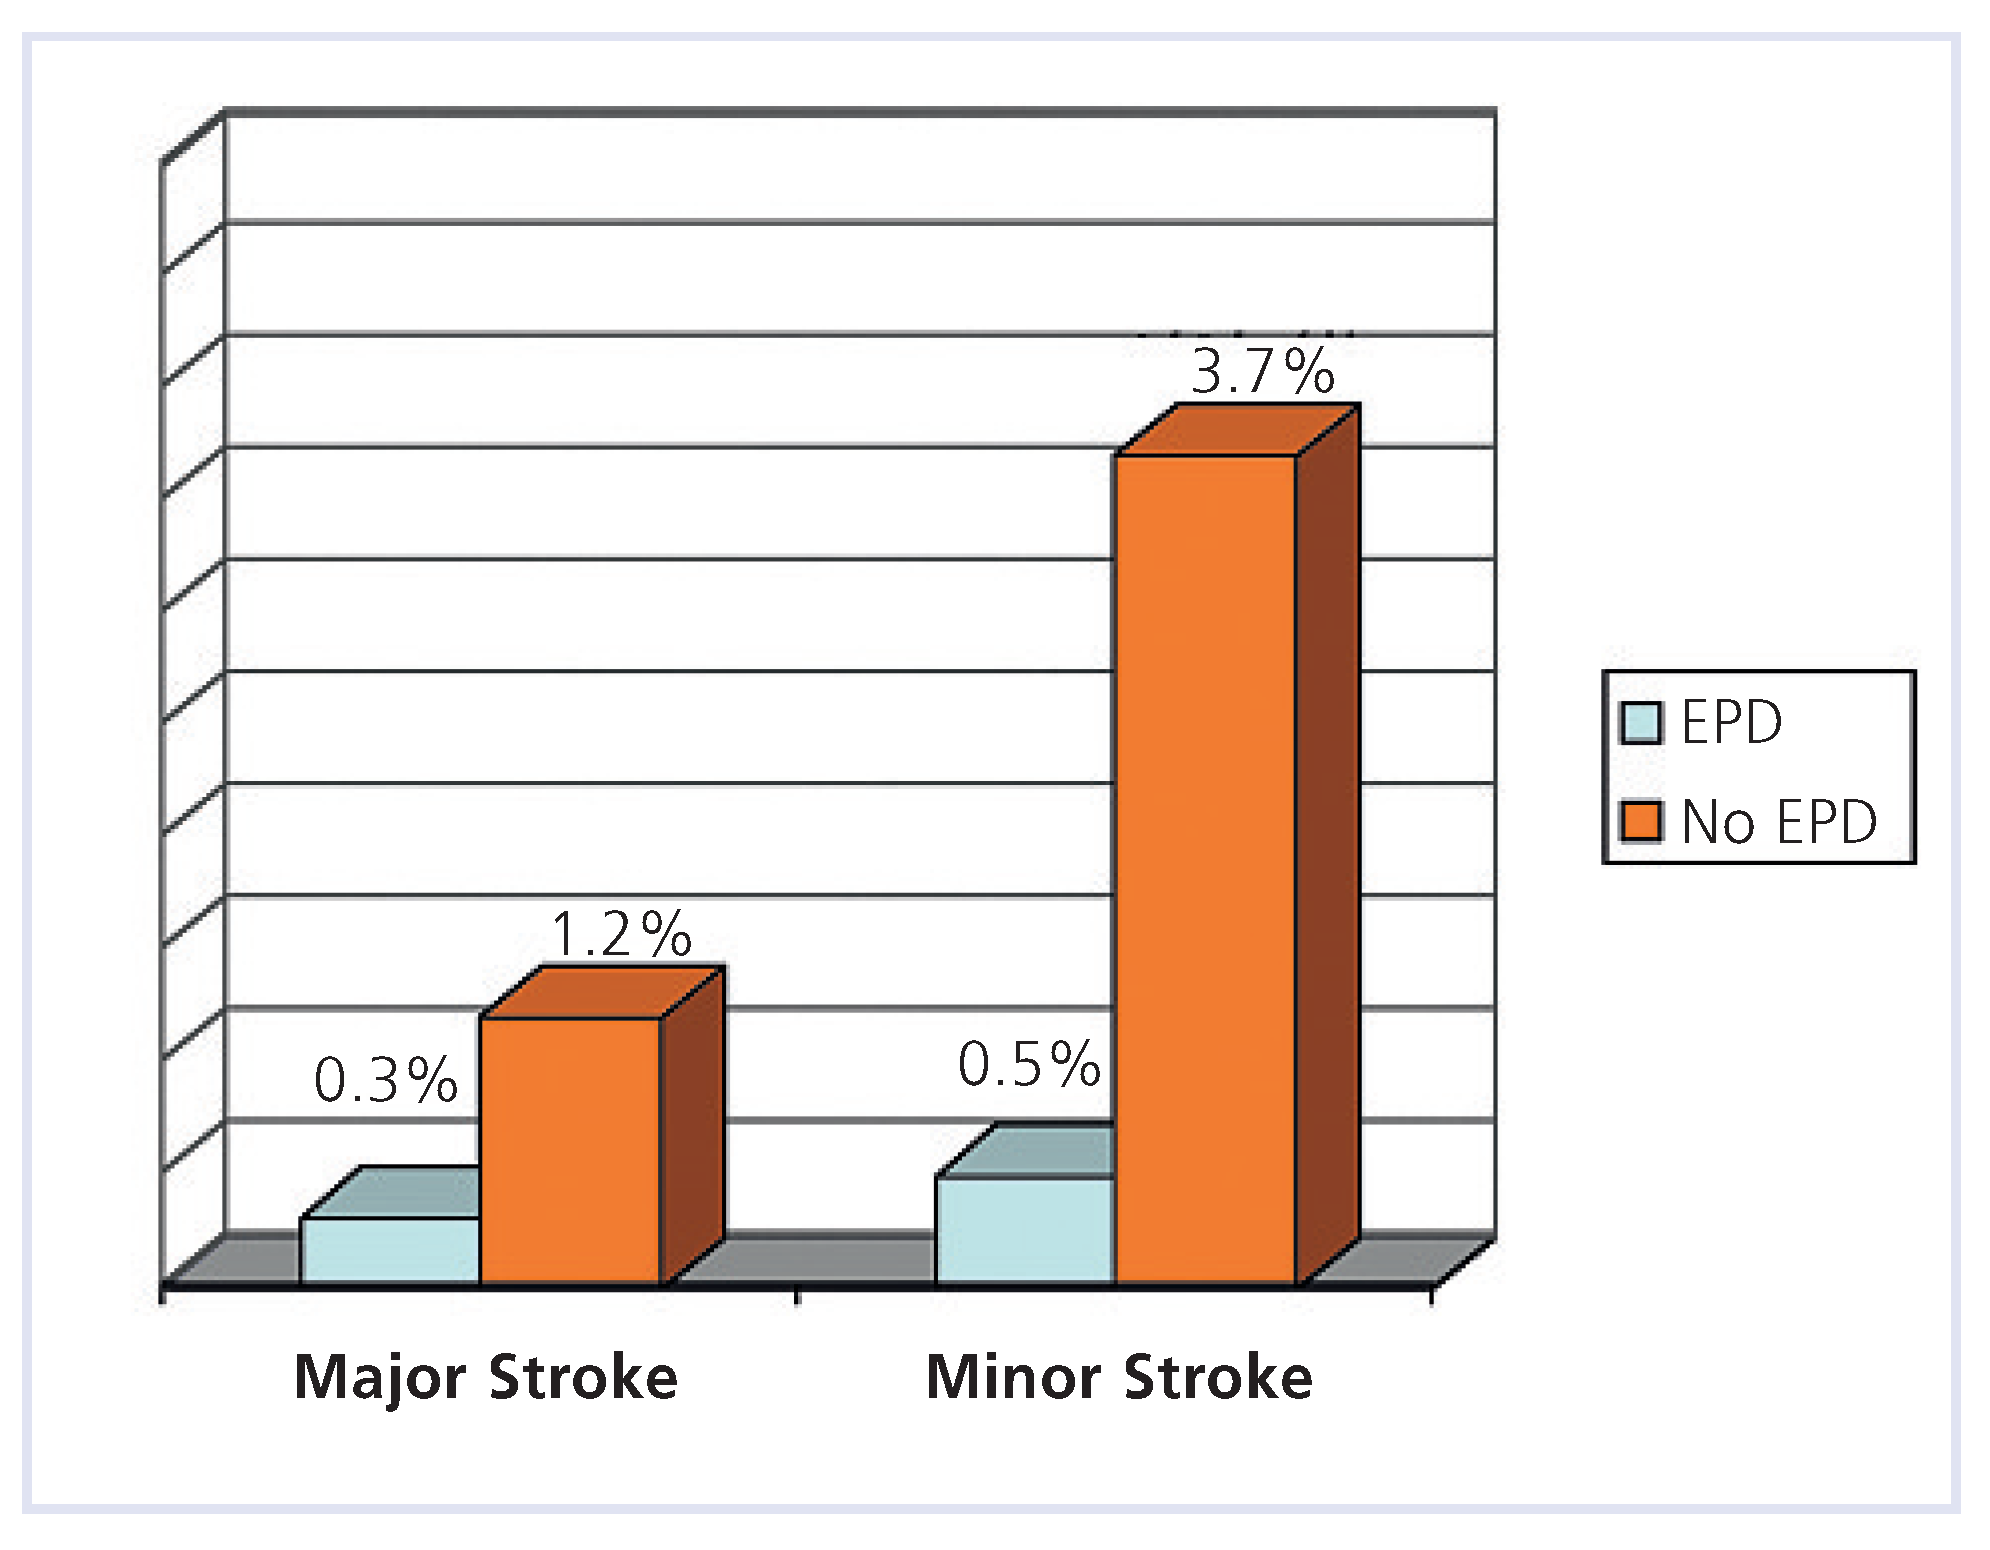

Carotid artery stenting

- Kastrup, A.; Groschel, K.; Krapf, H.; Brehm, B.R.; Dichgans, J.; Schulz, J.B. Early outcome of carotid angioplasty and stenting with and without cerebral protection devices: a systematic review of the literature. Stroke. 2003, 34, 813–819. [Google Scholar]

- Zahn, R.; Mark, B.; Niedermaier, N.; Zeymer, U.; Limbourg, P.; Ischinger, T.; et al. Embolic protection devices for carotid artery stenting: better results than stenting without protection? Eur Heart J. 2004, 25, 1550–1558. [Google Scholar] [CrossRef]

- Ouriel, K.; Wholey, M.H.; Fayad, P.; Katzen, B.T.; Whitlow, P.; Frentzko, M.; et al. Feasibility trial of carotid stenting with and without an embolus protection device. J Endovasc Ther. 2005, 12, 525–537. [Google Scholar] [CrossRef]

- Zahn, R.; Ischinger, T.; Mark, B.; Gass, S.; Zeymer, U.; Schmalz, W.; et al. Embolic protection devices for carotid artery stenting: is there a difference between filter and distal occlusive devices? J Am Coll Cardiol. 2005, 45, 1769–1774. [Google Scholar] [CrossRef]

- Cremonesi, A.; Manetti, R.; Setacci, F.; Setacci, C.; Castriota, F. Protected carotid stenting: clinical advantages and complications of embolic protection devices in 442 consecutive patients. Stroke. 2003, 34, 1936–1941. [Google Scholar] [CrossRef] [PubMed]